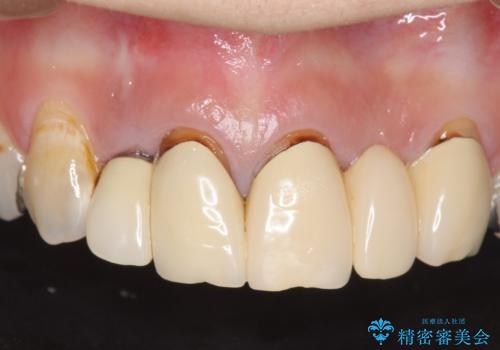

→根管治療完了後、土台を築造し、かぶせ物を製作してかみ合わせを回復する

すでに感染が根の先端まで及んでいたため、かなり強い痛みがありましたが、丁寧に根管治療をすることで内部を可及的に無菌化し、痛みが消失しました。

かぶせ物の種類:Bellezza